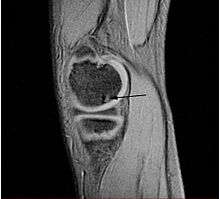

Magnetic resonance imaging (MRI) is useful for staging OCD lesions, evaluating the integrity of the joint surface, and distinguishing normal variants of bone formation from OCD by showing bone and cartilage edema in the area of the irregularity. MRI provides information regarding features of the articular cartilage and bone under the cartilage, including edema, fractures, fluid interfaces, articular surface integrity, and fragment displacement.[36][37] A low T1 and high T2 signal at the fragment interface is seen in active lesions. This indicates an unstable lesion or recent microfractures.[29] While MRI and arthroscopy have a close correlation, X-ray films tend to be less inductive of similar MRI results.[37]